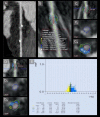

Purpose: Coronary bioresorbable stents (BRS) do not produce blooming artifacts on computed tomography (CT), in contrast to metallic stents, as they are made of a bioresorbable polymer and are radiolucent. They allow to evaluate the coronary plaque beneath. The low-attenuation plaque (LAP) suggests plaque vulnerability and is CT assessable. The aim of our study was to show the possibility of a non-invasive CT evaluation of the volume and the LAP composition of the intra- and juxta-stent plaque.

Methodology: In our prospective longitudinal study, we recruited 27 consecutive patients (35 BRS stents total; mean age 60 +/- 9 years) with bioresorbable stents for a 256-slice ECG-synchronized CT evaluation at 1- and 12-months post stent implantation. Total plaque volume (mm3), absolute and relative (%) LAP volume per block in the pre- intra- and post-stent zones were analyzed; comparison 1- and 12-months post-implantation of BRS. Changes in the previously mentioned variables were assessed by the mixed effects models with and without spline, which also accounted for the correlation between repeated measurements.

Results: Our block or spline model analysis has shown no significant difference in plaque or absolute LAP volumes in pre- intra- and post-stent zones between 1 and 12 months. Interestingly, % LAP volume increases near-significantly in the distal block of the intrastent at 12-mo follow-up (from 23.38 ± 1.80% to 26.90 ± 2.22% (increase of 15%), p = 0.052).

Conclusion: Our study demonstrates the feasibility of the repeated non-invasive quantitative analysis of the intrastent coronary plaque and of the in-stent lumen by CT scan.